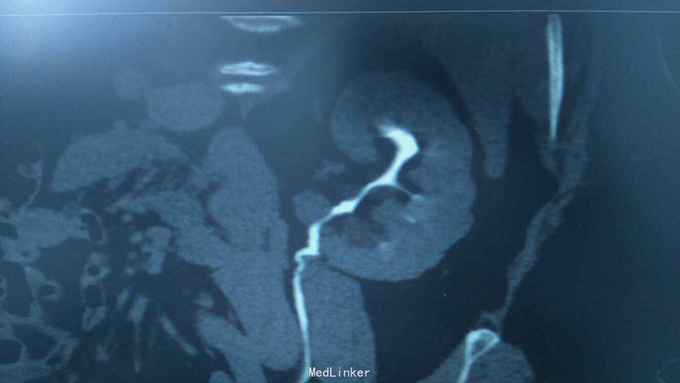

68岁,女性。 主诉:左侧腰痛1年,加重1个月。 病史:1年前无明显诱因出现左侧腰痛,无恶心呕吐,无肉眼血尿。1个月前加重,于外院查泌尿系彩超显示:左肾积液,输尿管显示不清。

诊断:双肾盂旁囊肿 治疗:因患者肾盂未明显受压,疼痛症状不明显,等待观察,暂未予处理。

双侧同时出现的病例并不多见,临床只能通过泌尿系统CTU或增强CT加以鉴别,彩超无法区分肾盂积水及盂旁囊肿。